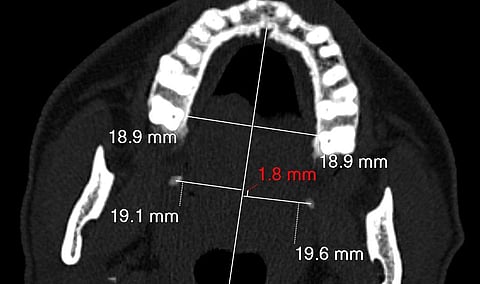

وبيّنت أن التشخيص تم باستخدام تقنيات إشعاعية وسريرية متقدمة، إلى جانب ابتكار طبي سعودي جديد يتمثل في رسم خط وهمي على الأشعة الطبقية المحورية، أُطلق عليه اسم "Bin Turayki’s Line"، تكريمًا للدكتور بن تريكي، ليسهّل عملية التشخيص في الحالات المشابهة حول العالم.

وأشارت الدراسة التي نُشرت في مجلة علمية مرموقة إلى أن التدخل الجراحي لإزالة العظم الزائد في الحنك العلوي كان هو الخيار العلاجي الأنسب، وأسفر عن تحسن جذري في الحالة الصحية للمريضة، واختفاء الآلام بشكل ملحوظ.